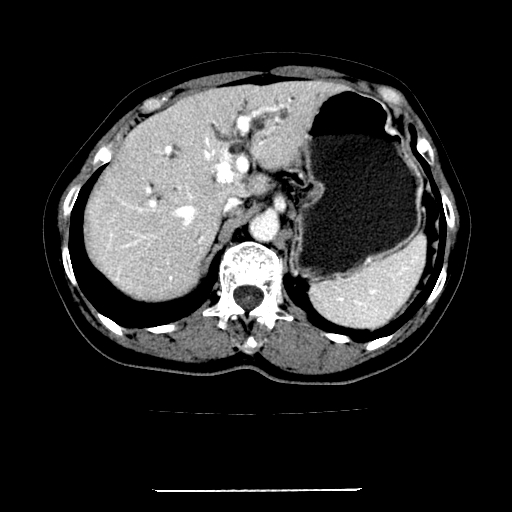

标题: CT22301:女,67岁,上腹部疼痛一周伴皮肤黄染,无发热。 [打印本页]

女,67岁,上腹部疼痛一周伴皮肤黄染,无发热。

左叶肝内胆管结石,并远端肝内胆管扩张。

考虑:肝内胆管结石继发肝内胆管扩张,右肾旋转不良。

肝内外胆管结石并肝内胆管扩张。

肝内外胆管结石并肝内胆管扩张

肝内外胆管扩张,左叶胆管内结石

建议薄层观察,除外肝门部胆管细胞癌

考虑肝胆管癌;胰头占位?【形态失常,体积增大】

1、肝门高密度影下层面和胰头层面可见轻度胆管扩张,而静脉和延迟期均未见扫描完胰头,不能完全排除胰头占位。2、肝门部高密度影,考虑钙化或结石。

考虑肝门胆管癌伴门脉左支受侵包埋,建议mrcp进一步检查。

肝内胆管结石并胆管扩张